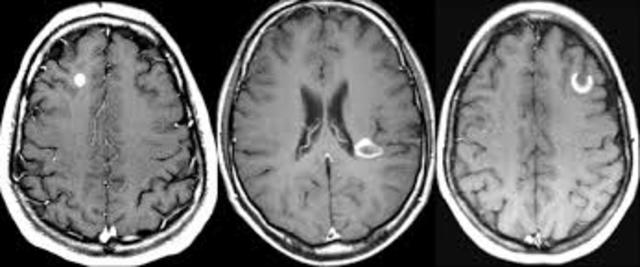

• Imágenes funcionales

Imágenes funcionales

se fortalece la investigación con el empleo de imágenes funcionales, en particular la resonancia magnética funcional y la tomografía por emisión de positrones (PET), que han permitido visualizar la actividad cerebral durante la realización de diferentes tareas cognoscitivas. Asimismo, surge un nuevo modelo

en la interpretación de la organización cerebral de la cognición, el denominado “modelo funcional”. Hasta este momento se había utilizado un “modelo lesional”